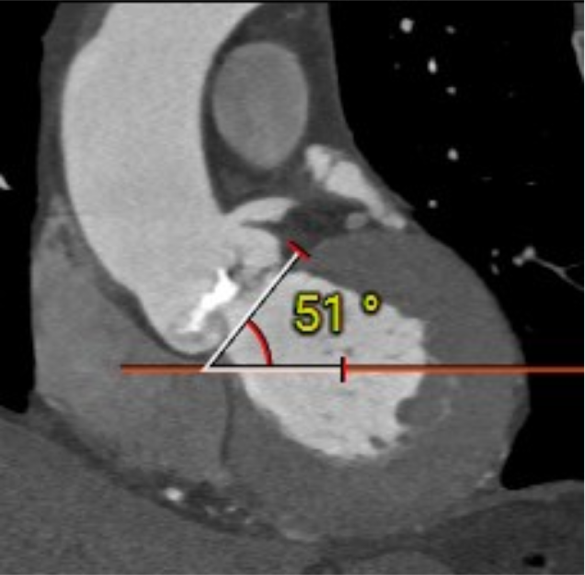

心室角度51度: